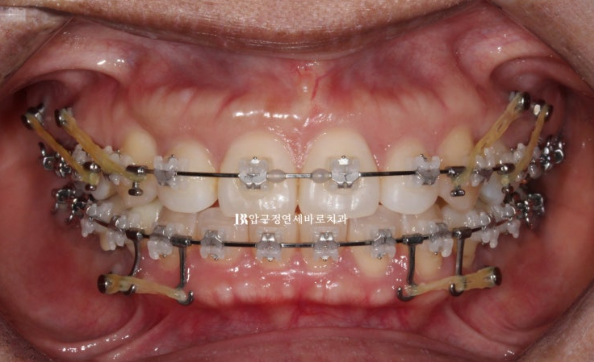

클리피씨로 치료하기로 하고 미니스크류를 위에 4개 아래 2개 총 6개를 식립하고 치료를 진행했습니다.

아래는 전체 치열을 뒤로 밀고 위에는 전체치열을 뒤로도 밀고 위로도 밀어올립니다.